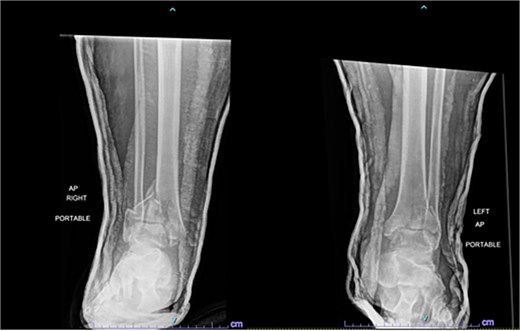

A 57-year-old male with a body mass index (BMI) of 48.7 kg/m2 and multiple comorbidities, including asthma, coronary artery disease, hypertension, hyperlipidemia, ischemic cardiomyopathy, obstructive sleep apnea, and hypothyroidism, following a motor vehicle collision when he lost control of his vehicle due to a coughing spell. His injuries included bilateral pilon fractures (Fig. 1), a T2 superior endplate fracture, and bilateral pulmonary contusions. He initially presented to a regional hospital and was transferred to our facility 10 days after the injury.

Anterior-to-posterior (AP) radiographs of patient 1 obtained 10 days after injury, upon transfer to our facility, demonstrating bilateral pilon fractures.